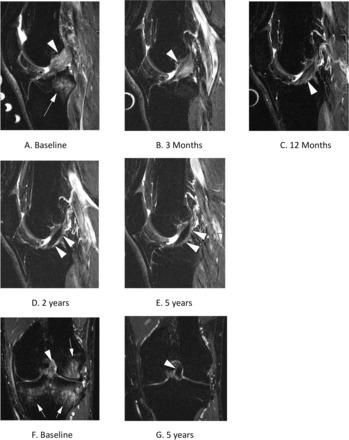

FISIOTERAPIA EUO🦶🦵